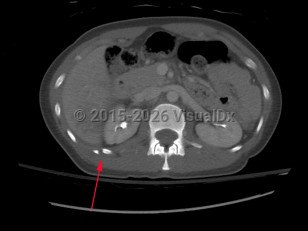

Causes / typical injury mechanism: Rib fractures are a common injury of the thoracic cage. They may be traumatic or pathologic. Depending on the location and the number of ribs involved, be alert for possible visceral injuries, pulmonary contusions, pneumothorax, or vascular injury.

Fractures of the lower ribs (9-12) could indicate concomitant intraabdominal injury.

- Presence or absence of visceral injury